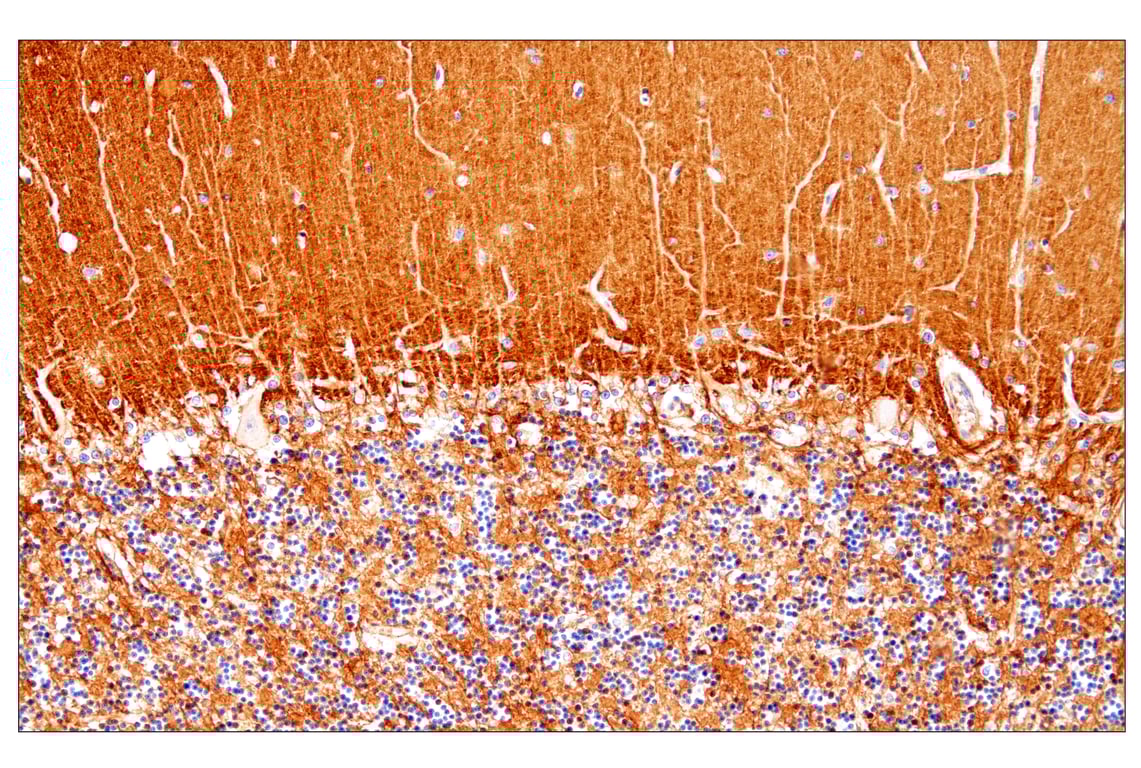

Immunohistochemistry (Paraffin) 1:500 - 1:2000

PTPRZ1 (E7C8Z) Rabbit Monoclonal Antibody detects endogenous levels of total PTPRZ1 protein. Non-specific staining was observed in mouse kidney tubules by immunohistochemistry.